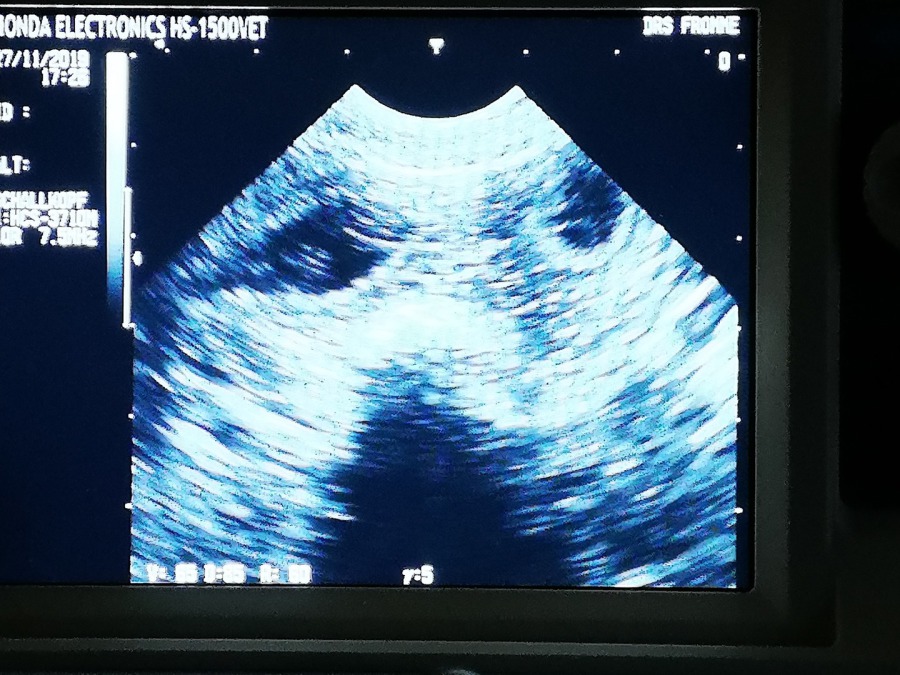

Hallo ihr Lieben :-) Wir hatten ja heute den Ultraschal Termin und was soll ich sagen, ich erwarte wieder kleine Krümelchen :-) Ich habe es natürlich schon die ganze Zeit gewusst, aber meine Zweibeiner ja nicht und ich sage euch, die freuen sich schon soooooo sehr auf meine Kleinen :-) Ich lag auch total entspannt und völlig gelassen auf der Matte, die immer auf den Tisch gelegt wird, sodass die Zweibeiner alles gut sehen können, also 6 Krümel haben sie sicher gesehen, es können aber auch leicht noch mehr sein, sie sind ja noch klein und manchmal verstecken sich die süßen hinter meinem Darm und können so natürlich auch nicht gesehen werden ;-) Es bleibt also spannend, wie viele es genau werden :-) Mein liebes Frauchen Marion hat sich auch gleich an den Computer gesetzt und leckeres Futter für mich bestellt, denn das muss jetzt ja langsam erhöht werden, was ich natürlich super finde, denn ich esse für mein Leben gerne :-) Das Futter, welches ich dann bekomme ist das Starter Futter von Royal Canin, extra für Welpen und werdende Mütter und ich sage euch, dieses Futter ist ein Gaumenschmaus :-) So viel also für heute, ich gehe mich jetzt erstmal etwas ausruhen und freue mich schon aufs Abendessen :-)   Vielen Dank euch allen für das fleißige Daumendrücken, ihr könnt aber gerne witerdrücken. Schließlich steht die Geburt ja noch an, aber bis dahin dauert es noch etwas :-)                                                                                                              Ich melde mich bald wieder  :-)                                                                                    Euch noch eine schönen Abend                                                                                                P.S. auf dem Bild sind übrigens 3 Würmchen zu sehen ;-)

Hier sind 2 Krümel zu sehen, das dunkle schwarze unten ist meine Blase :-)